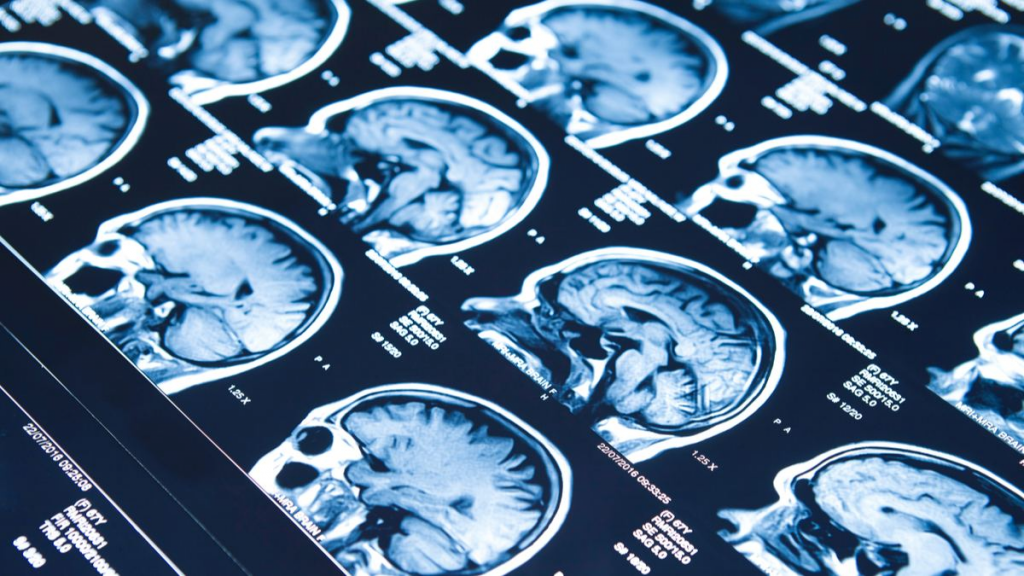

Un equipo de la Universidad de Yale (EE.UU.) ha descubierto que los bebés sí pueden formar recuerdos específicos, lo que...